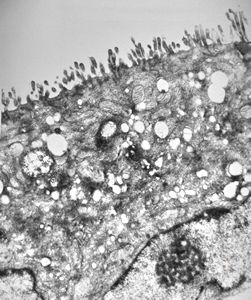

normal mucosa - jejunum - microvilli(anchored core rootlets)

normal mucosa - jejunum - microvilli